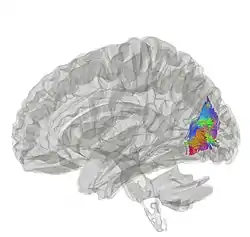

The vertical occipital fasciculus is a fascicle of white matter running vertically in the rear of the brain. It is found at least in primates. It "is the only major fiber bundle connecting dorsolateral and ventrolateral visual cortex."[1]

The vertical occipital fasciculus consists of long nerve fibers making connections between vision sub-regions in the rear of the brain. Research indicates that it is related to both vision and cognition, since injury to it can cause reading impairment.[6]